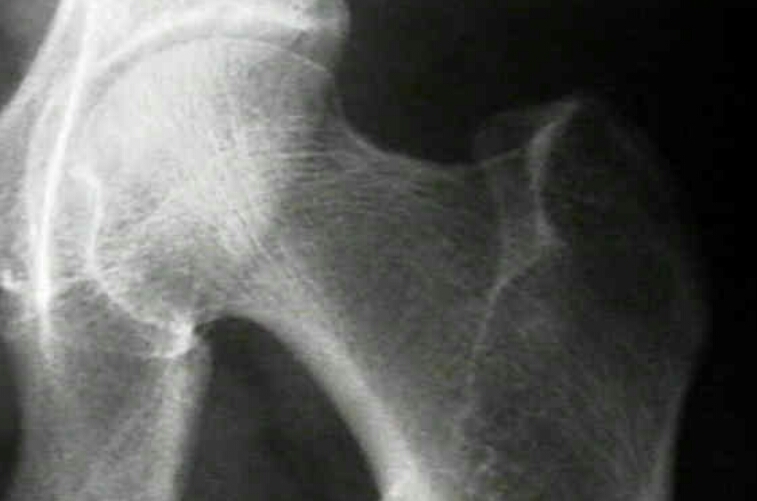

What is the radiographic feature? How does this occur?

Ward’s triangle

occurs when primary and secondary compressive and primary tensile trabecular patterns of the hip wither away at about the same time